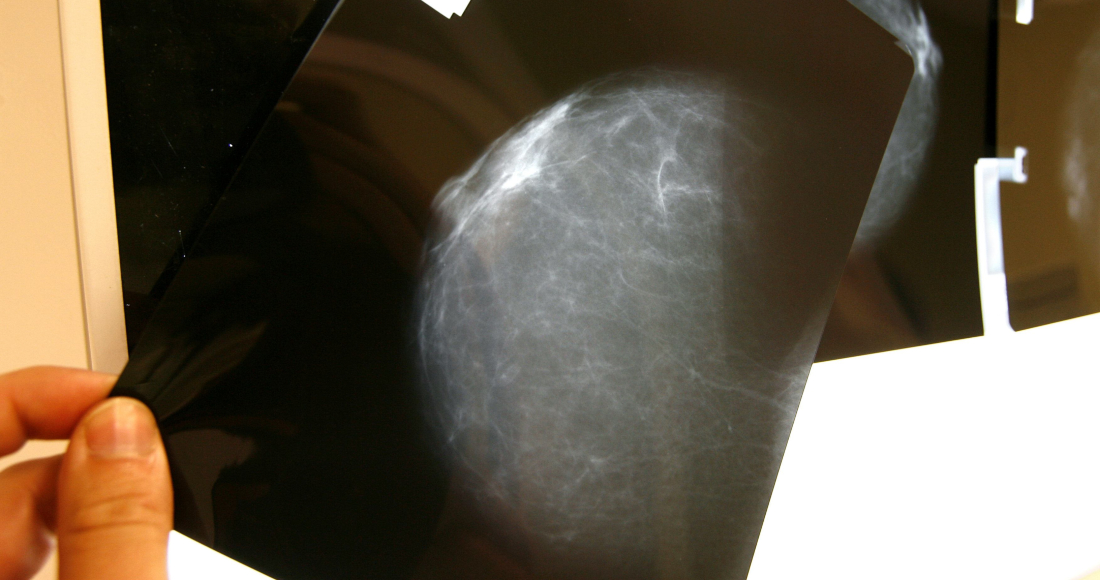

México, 27 septiembre (EFE).- Las pacientes con cáncer de mama presentan problemas psicosociales asociados a esta enfermedad, pero recibir un apoyo integral les ayuda a mejorar su autoestima, según un estudio presentado este jueves en la Ciudad de México.

De acuerdo con el estudio "La activación del paciente con diagnóstico de cáncer y su asociación con variables psicosociales" presentado por la Fundación Voluntarias contra el Cáncer, se demostró que los efectos negativos de quien padece esta enfermedad impactan en lo biológico, psicológico y social.